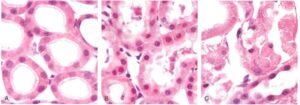

In realtà, non tutte le LOR registrate sono generate da conteggi veri. La figura accanto mostra quattro possibili tipi di eventi di coincidenza che possono essere registrati durante una scansione PET.

L’evento che ha origine nel punto 1 corrisponde a un conteggio vero (T) tra i rivelatori i e j, generando quindi un conteggio nella LORij. Invece, almeno uno dei due fotoni γ emessi dalla posizione 2 subisce uno scattering Compton lungo il suo percorso, e il conteggio corrispondente nella LORkl considera un’annichilazione che non avviene lungo la stessa linea di risposta. Questo tipo di evento è chiamato conteggio scatter (S). Un terzo tipo di evento è chiamato conteggio random (R). È generato quando due fotoni vengono emessi da due punti diversi (ad esempio, i punti 3 e 4 nella figura), e vengono registrati, in coincidenza temporale, nei rivelatori che definiscono una LOR geometricamente accettabile. Tutti i tipi di conteggi T, S e R sono genericamente chiamati conteggi prompt (P), ma solo i conteggi veri contengono informazioni utili per la ricostruzione dell’immagine.